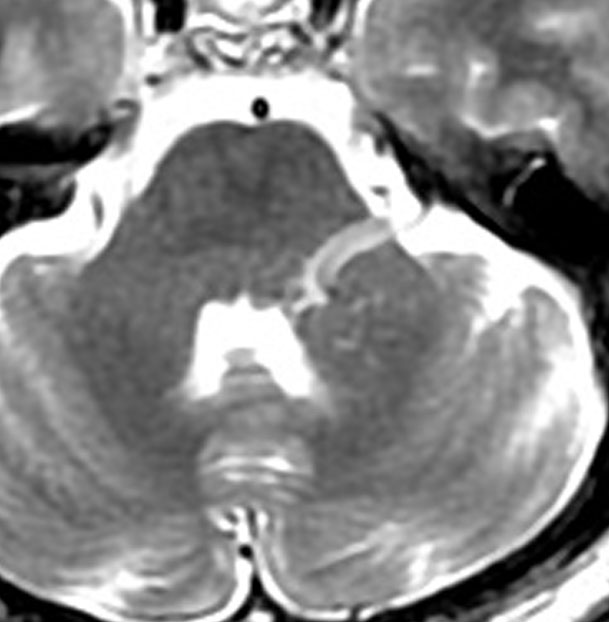

左側と中央は正常な人の三叉神経です。

右側のMRIは後頭骨がとても小さい女性です。三叉神経の周りの隙間(髄液腔)がほとんどなくて三叉神経がよく見えません。14歳で右三叉神経痛を発症しました。治すための神経血管減圧術はとても難しいと言えます。場合によっては,隙間を作るために錐体骨尖部の骨をドリルで削らなければならい事もあります。

日本人には,頭蓋骨が小さいため脳と神経の隙間が狭くて,ギューギューづめの状態で血管が三叉神経や顔面神経にぶつかりやすい人が多いです。特に,顔面けいれんは頭蓋骨の小さな日本人女性に多いと言えます。